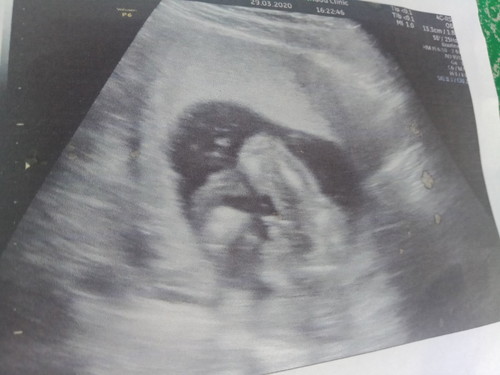

ในรูปไปซาวด์ดูเพศตอนอายุครรภ์4เดือน แต่ในใจแม่แอบหวังลูกสาวนิดๆ แม่ๆดูแล้วคิดว่าน้องเป็นเพศหญิงหรือชายคะ.